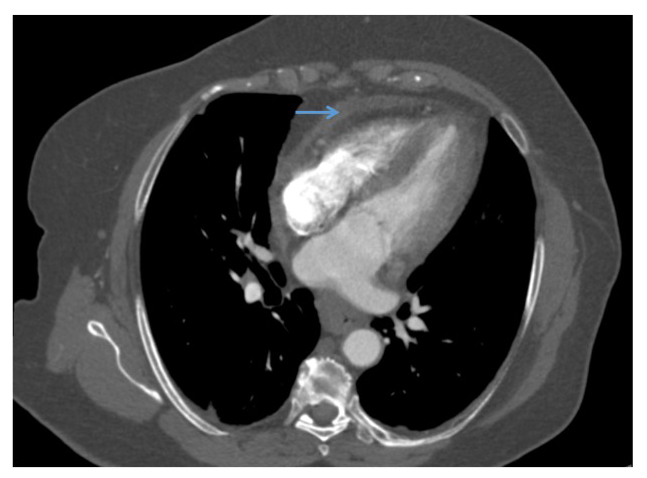

Chest Pain Following Aortic Valve Replacement American College

Http Pdf Posterng Netkey At Download Index Php Module Get Pdf By Id Poster Id 115936